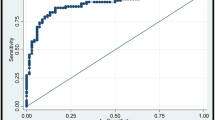

Shear wave elastography (SWE) is an emerging technique which can obtain quantitative elasticity values in breast disease. We therefore evaluated the diagnostic performance of SWE for the differentiation of breast masses compared with conventional ultrasound (US). Conventional US and SWE were performed by three experienced radiologists for 158 consecutive women who had been scheduled for US-guided core biopsy or surgical excision in 182 breast masses (89 malignancies and 93 benign; mean size, 1.76 cm). For each lesion, quantitative elasticity was measured in terms of the Young’s modulus (in kilopascals, kPa) with SWE, and BI-RADS final categories were assessed with conventional US. The mean elasticity values were significantly higher in malignant masses (153.3 kPa ± 58.1) than in benign masses (46.1 kPa ± 42.9), (P < 0.0001). The average mean elasticity values of invasive ductal (157.5 ± 57.07) or invasive lobular (169.5 ± 61.06) carcinomas were higher than those of ductal carcinoma in situ (117.8 kPa ± 54.72). The average mean value was 49.58 ± 43.51 for fibroadenoma, 35.3 ± 31.2 for fibrocystic changes, 69.5 ± 63.2 for intraductal papilloma, and 149.5 ± 132.4 for adenosis or stromal fibrosis. The optimal cut-off value, yielding the maximal sum of sensitivity and specificity, was 80.17 kPa, and the sensitivity and specificity of SWE were 88.8% (79 of 89) and 84.9% (79 of 93). The area under the ROC curve (Az value) was 0.898 for conventional US, 0.932 for SWE, and 0.982 for combined data. In conclusion, there were significant differences in the elasticity values of benign and malignant masses as well as invasive and intraductal cancers with SWE. Our results suggest that SWE has the potential to aid in the differentiation of benign and malignant breast lesions.